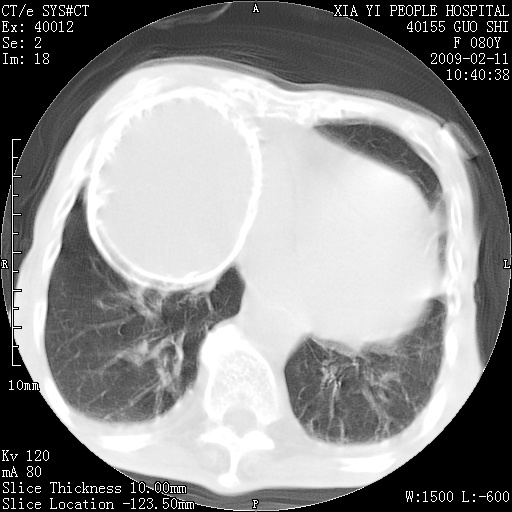

以下是引用随光逐影在2009-2-16 16:34:00的发言:[br]1)考虑右前纵隔皮样囊肿。2)双侧少量胸腔积液。

以下是引用zjzjr在2009-2-16 17:30:00的发言:[br]支持囊性畸胎瘤 双侧少量胸腔积液。